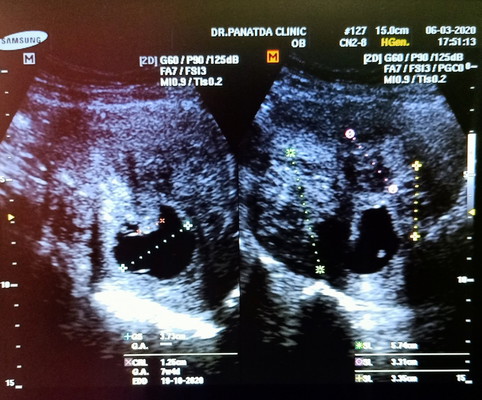

ท้องลม & เนื้องอก

มีใครเคยท้องลม แล้ว เป็นเนื้องอกในมดลูกแบบเราบ้างไหมคะ